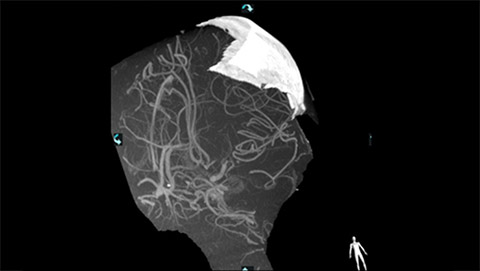

VasoCT (Allura X-ray system with dedicated EPX settings + XperCT + intravenous contrast injection) provides high-resolution imaging of intracranial arteries to help visualize location, size, and direction of an occlusion in case of Ischemic Stroke.

VasoCT visualizes small intra-cranial devices in vessel context with unmatched spatial resolution. Metal Artifact Reduction decreases streaking artifacts as from coil mass close to intra-cranial devices.